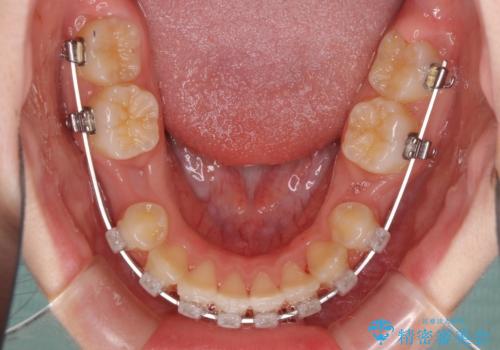

乳歯が残っている 目立たない装置での抜歯矯正

- クリアブラケット

- 八重歯と乳歯が残っていることを気にして来院された患者様です。

乳歯が3歯残っており、下顎は左右ともに後続永久歯がない状態でした。

口元が突出しており、口が閉じにくかったため、乳歯を含め上下5歯を抜歯して矯正治療を行うこととしました。

下顎の乳歯は永久歯と比べて幅が大きいため、抜歯した場合のスペースが大きく、治療には長期間を要することが一般的です。

今回の患者様は中学生ということもあり、成人の患者様と比べ動きが速く、2年間で治療を終えることができました。